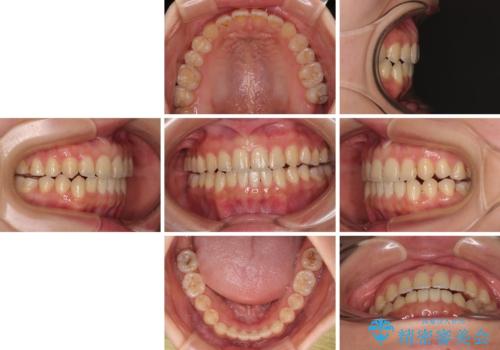

前歯のオープンバイト インビザラインで咬み合わせを改善

- 前歯の開咬を気にして来院された患者様です。

開咬の治療は、前歯を閉じるように動かすとともに、上下臼歯を圧下(骨内にめり込ませる)させることで進めて行きます。

インビザラインは臼歯の圧下を効果的に行えるため、インビザラインを用いて矯正治療を行うこととしました。